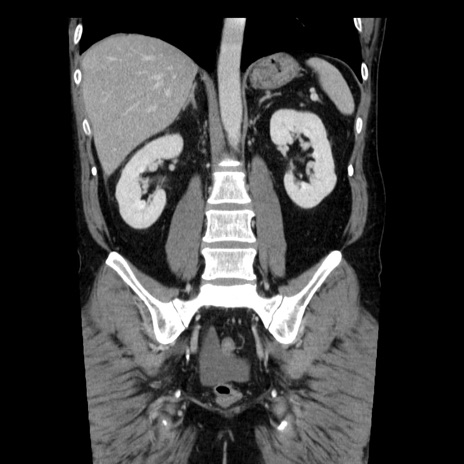

症例29(冠状断像)

【症例】40歳代男性

【現病歴】2日前から胃痛あり。徐々に周期的な激痛に変化した。本日になっても激痛があるため受診。

【身体所見】意識清明、BT 38-39℃台あり、腹部:膨満、やや硬、右下腹部に圧痛あり。

【データ】WBC 8500、CRP 23.26